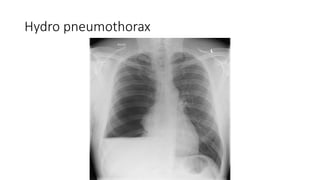

Hydro pneumothorax